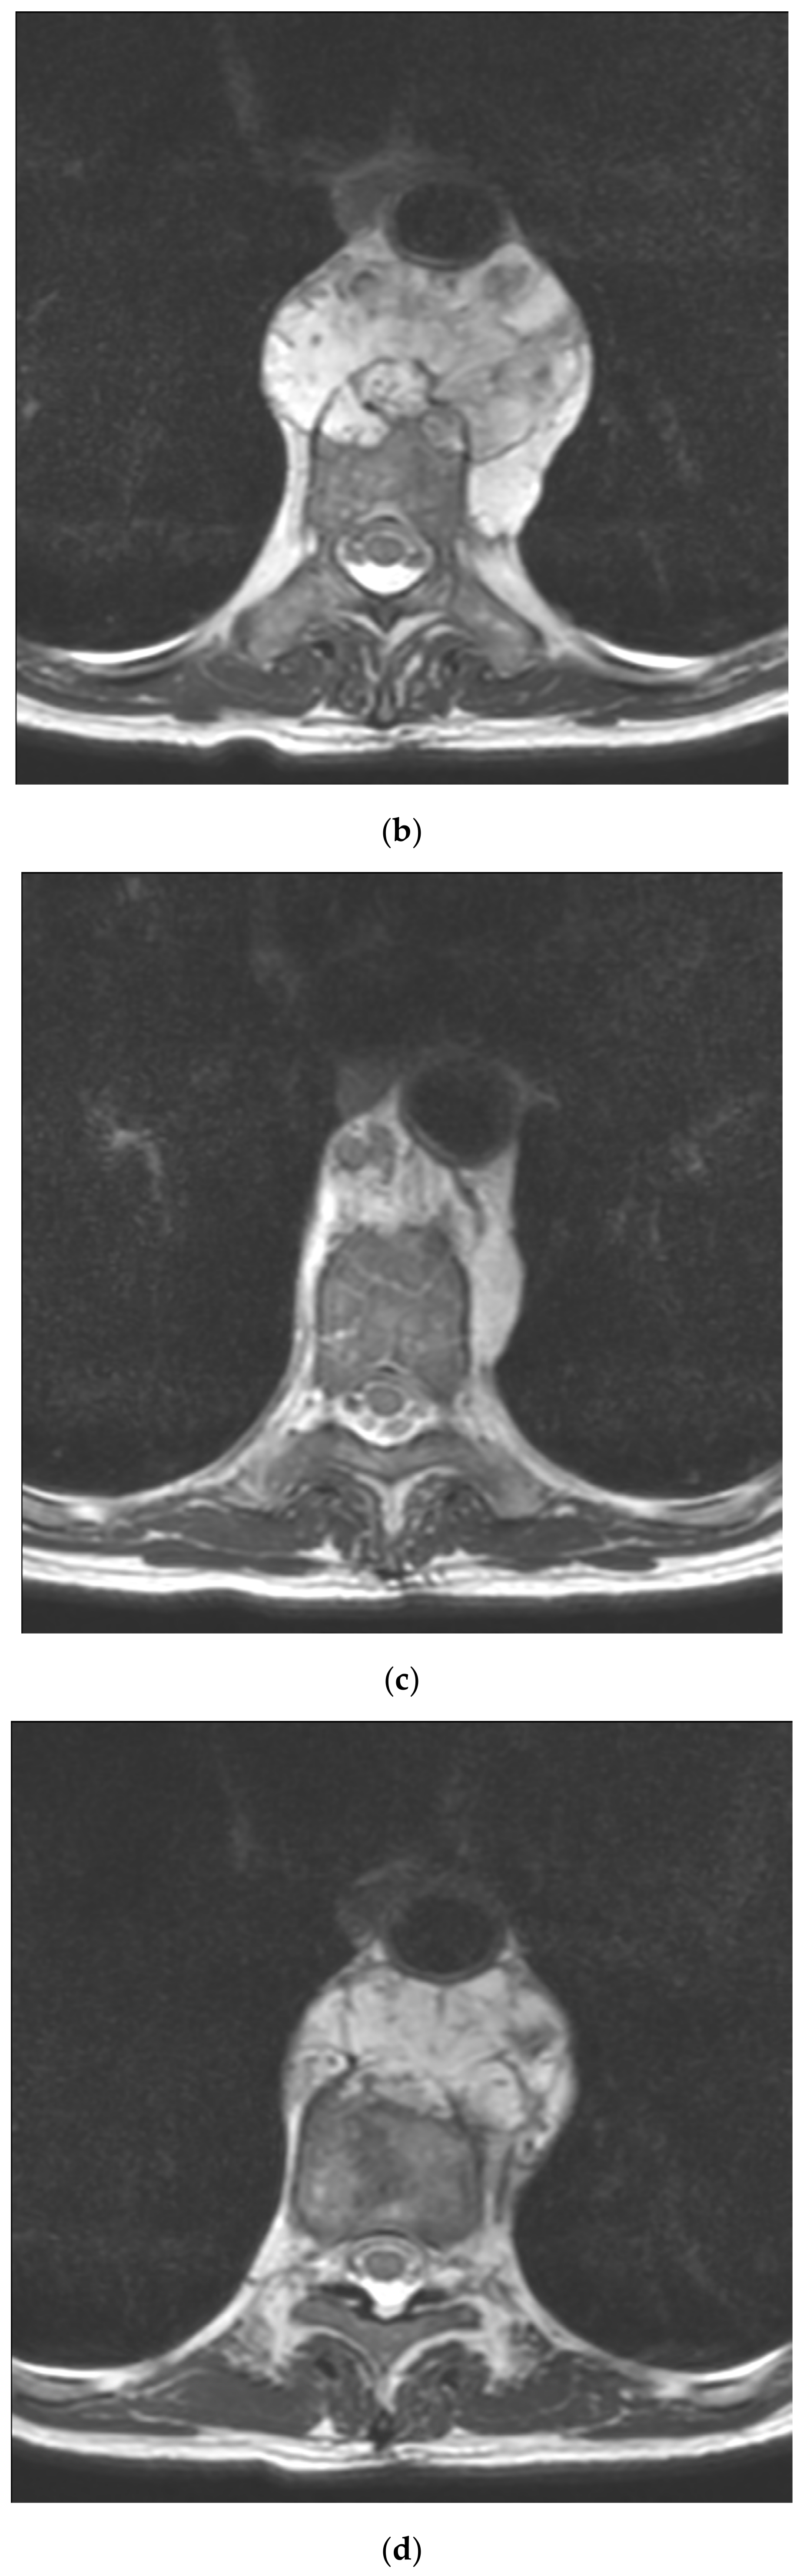

2.2. Imaging Studies